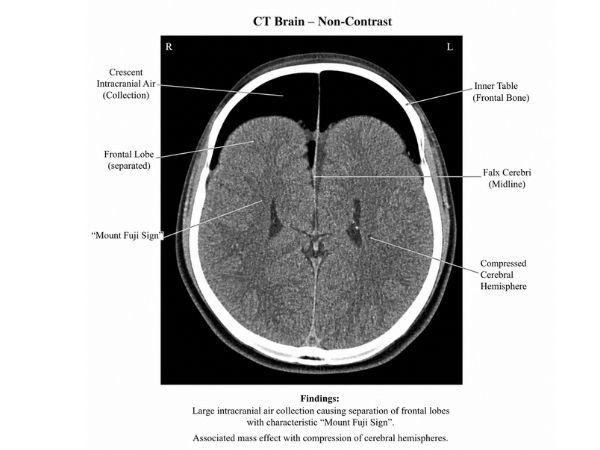

The Mount Fuji Sign in Tension Pneumocephalus is a classic result on a CT scan of the brain.

On imaging, the brain’s frontal lobes resemble the silhouette of Japan’s well-known Mount Fuji, appearing crushed and divided by air.

The gold standard for diagnosis is a non-contrast CT scan of the brain.

Important CT results:

- Intracranial air presence

- Frontal lobe separation

- Brain structure compression

- The Mount Fuji sign’s appearance

A Mount Fuji Sign in Tension Pneumocephalus indicates a neurosurgical emergency. The goal of treatment is to release trapped air and reduce pressure.